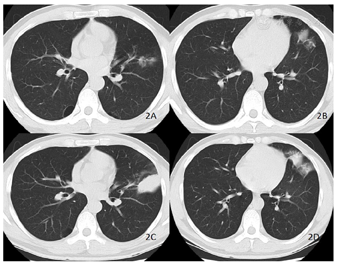

胸部CT检查:左肺上叶上舌段支气管狭窄,远端病变,考虑恶性病变可能;纵隔4 L、10 L淋巴结饱满;双肺多发间隔旁肺气肿;气管憩室。2022年4月14日胸部CT较2022年3月29日胸部CT左肺上叶病大(图2)。